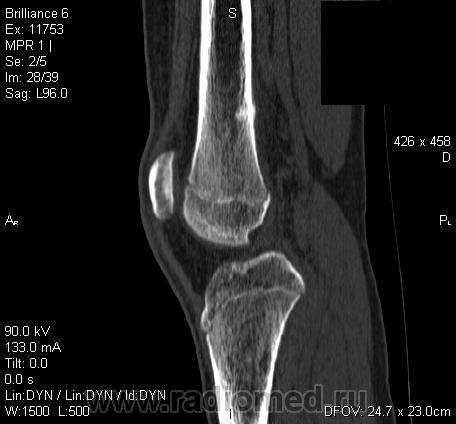

Да, на мой взгляд, состояние после обычного "травматического перелома" (трещина), не думаю, что имел место "патологический перелом", так как костная ткань "патологически изменена" минимально. "Перистальная реакция"локальная тоже есть, на КТ "локальная  зона склероза" - все это свидетельствует именно об этом. Хотя в памяти у меня хорошо отложился Ваш последний случай о локальном утолщении кортикального слоя, когда "яйца в гнезде" еще не было. То, что анамнестически "травмы не было" - ничего не значит. Вы, по всей видимости, тоже часто встречались с такими случаями, когда ребенок не акцентировал внимание на "травме", как таковой, хотя клиника есть, боль есть. Конечно, рентгенограммы - не дай бог - ни скиалогии, ни структуры.

Локальный гиперостоз, выраженный болевой синдром, структура губчатого вещества диафиза не изменена наводит только на остеойд-остеому.

Согласна с Ola-la - рентгенологическая картина более всего соответствует стрессорному перелому, хотя для него характерна локализация в б/берцовой кости. Меня однако, смущает и настораживает клиника - это как раз тот случай, когда я бы не дала 100% гарантии, что так не может манифестировать остеосаркома... Поскольку другие методы (МРТ, сцинтиграфия) вряд ли помогут, я бы взяла пациента на короткое ( 2недели - месяц) динамическое наблюдение.

Буквально заключение гистологов передать не могу (мой недочет, нужно было сразу выложить на сайтОй-ой-ой), но приблизительно помню - данных за специфический процесс нет, картина консолидирующегося перелома.

Так что, по всей видимости, это действительно был стресс-перелом. Который крайне редко встречается. Хоть статейку в журнал пишиУлыбаюсь.